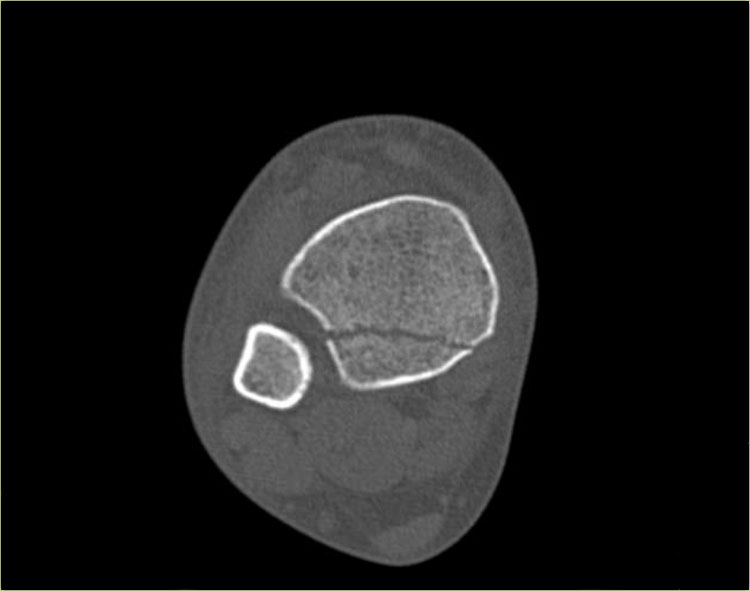

Đây là hình ảnh của một ca bệnh cực kỳ khó.

Bệnh nhân nữ bị bong gân cổ chân và đau cả hai bên trong và ngoài.

Bệnh nhân được bác sĩ đa khoa chuyển đến khoa Chẩn đoán Hình ảnh.

Kỹ thuật viên chụp các tư thế chuẩn gồm thẳng (AP), Mortise và nghiêng, sau đó trình bày cho bác sĩ X-quang, người đã khá băn khoăn khi đọc phim.

Hãy đọc hình ảnh trước, sau đó tiếp tục đọc phần giải thích.

Các dấu hiệu bao gồm:

-

Phù nề phần mềm cả hai bên trong và ngoài (mũi tên đỏ).

Đặc biệt, phù nề phía trong nên gợi ý khả năng chấn thương xoay ngoài – sấp (Weber C). - Đường thấu quang trên tư thế Mortise (mũi tên đen) và tư thế nghiêng. Dấu hiệu này nên gợi ý gãy tertius.

Bác sĩ X-quang quyết định chỉ định CT trước để xác định xem có thực sự có gãy tertius hay không.

Tiếp tục xem hình ảnh CT và bạn sẽ ngạc nhiên.

Hãy cuộn qua các lát cắt.

Thật đáng ngạc nhiên khi một mảnh tertius lớn như vậy lại rất khó nhìn thấy trên phim X-quang.

Cũng lưu ý phù nề phần mềm phía trong gợi ý đứt dây chằng bên trong (mũi tên).

Bạn có thể đoán được đây là loại chấn thương gì không?

Phù nề phần mềm phía trong và gãy tertius đều là dấu hiệu của chấn thương Weber C hoặc chấn thương xoay ngoài – sấp.

Do không thấy gãy xương mác trên phim X-quang cổ chân, phải có gãy xương mác cao.

Khi khám lâm sàng, có phù nề nhẹ phía trong và mặc dù bệnh nhân không than đau ở vùng cao hơn của cẳng chân, vẫn có điểm đau khi ấn vào xương mác.

Vị trí này được đánh dấu và phát hiện đường gãy.

Ca bệnh này minh họa tầm quan trọng của phù nề phần mềm phía trong cũng như dấu hiệu gãy tertius.

Theo phân loại Lauge Hansen, chúng ta có thể kết luận rằng bệnh nhân này đầu tiên bị đứt dây chằng bên trong (giai đoạn 1), tiếp theo là đứt dây chằng chày mác trước (giai đoạn 2), gãy xương mác cao (giai đoạn 3) và cuối cùng là bong mắt cá sau, tức là chấn thương xoay ngoài – sấp (PE) giai đoạn 4.

Trong phẫu thuật, cổ chân được xác định là không vững và vít cố định khớp chày mác đã được đặt vào.

Có chỉ định cố định gãy mắt cá sau vì mảnh gãy chiếm hơn 25% diện khớp của đầu dưới xương chày.